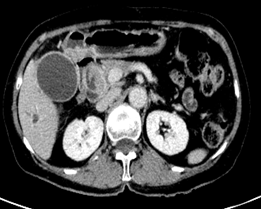

1.肝内型胆管细胞癌

CT、MRI:单发或多发低密度灶,边界不清,增强早期边缘强化,延迟期中央纤维间质进行性向心填充,周围呈相对低密度灶伴周围胆管扩张;薄膜回缩;肝叶萎缩。

肝内胆管细胞癌     肝外胆管细胞癌

病理提示①为肝内胆管细胞癌,②肝外胆管细胞癌